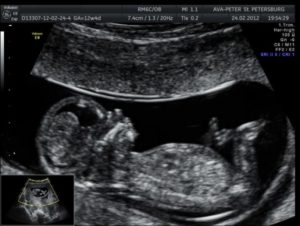

Поскольку при УЗИ 3 триместра многие показатели зависят от точного срока, важно, на какую неделю будет назначено обследование. Чаще всего врачи проводит процедуру на 32-34 неделе: на данном сроке ребенок принимает положение, в котором останется до самых родов, что позволяет решить, естественным способом женщина будет рожать или придется применять операцию кесарева сечения.

На 32 неделе длина тела ребенка должна варьироваться в пределах от 42,5 до 43,5 см. Масса тела составляет примерно 1790-1890 г. Головка в обхвате может быть от 29 до 33,2 см. К 33 неделе плод немного вырастает.

Если УЗИ проводилось на 34 неделе, младенец должен достигать в длину 44,5-45,5 см, весить 2,1-2,25 кг, окружность головы при этом может доходить до 33,9 см.

Выше уже упоминалось, что в период с 30 по 34 неделю беременности врачами определяется соответствие измеряемых показателей нормам по сроку. Иногда присутствуют отклонения на срок недели-двух, однако это нельзя считать показателем неправильного развития плода.

Сроки, в которые делают 3-е УЗИ по беременности, определяются медицинским стандартом ведения женщины.  Обследование проводится с 30-й по 34-ю неделю. Наиболее часто гинекологи назначают делать третий скрининг с помощью УЗИ в 32 недели гестации.

Плацента, или детское место, – орган, защищающий ребенка от инфекций, вирусов и вредных веществ, попадающих в организм матери во время беременности. В третьем триместре нужно оценивать состояние плаценты – толщину и степень зрелости. Это указывает на готовность к родам. Нормальные показатели в 32–34 недели беременности – 26–44 мм.

Также смотрят расположение плаценты. Чаще всего это передняя или задняя стенки матки. Если же она заходит на бока или опускается вниз, это требует особого внимания. Слишком низко опустившаяся плацента (менее 4 см от шейки матки) перекрывает ребенку выход из родовых путей, повышает риск кровотечения в родах. Это показание к кесареву сечению.

Результаты ультразвукового скрининга на этом сроке гестации содержат важные данные о развитии плода, состоянии «детского места», околоплодной жидкости и матки. В протокол исследования вносят параметры фетометрии:

• бипариентальный размер головы – его измеряют в поперечной плоскости от одной теменной косточки до другой (норма – от 77 см до 93)

• лобно-затылочный размер – расстояние измеряется от лобной косточки до затылка (98 –116);

• окружность головки (29 – 33,7), грудки и животика (26,5 – 22,5);

• длина предплечья, плечиков (54 – 65), бедер (56 – 59) и голеней (по размерам костей можно выявить генетические патологии);

• вес (от 1700 до 2150 г) и рост (42 – 45 см).

В связи с индивидуальными особенностями женского организма допускается отклонение от нормальных показателей УЗИ в 1-2 недели. Значительное снижение параметров может свидетельствовать о внутриутробной задержке развития плода. Для подтверждения диагноза проводятся дополнительные исследования.